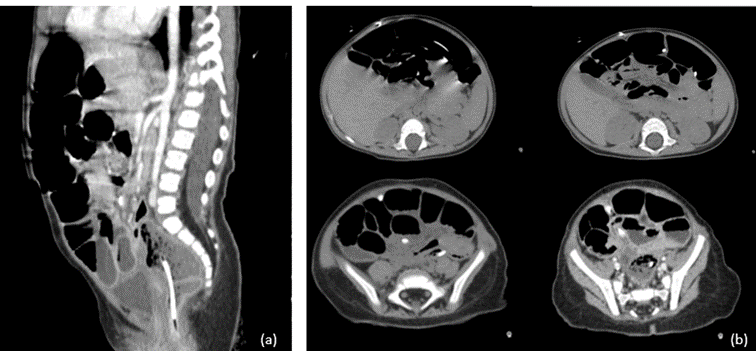

At four months post-surgery, the parents noted extrusion of the catheter tip through the anus (Figure 4). The child was afebrile, alert, and had no abdominal tenderness. CT and radiographs (Figures 5 and 6) revealed sigmoid perforation with intraluminal catheter migration into the rectum. Importantly, no pneumoperitoneum, abscess, or signs of peritonitis were present.

Figure 5: Abdominal CT scans demonstrating the distal cystoperitoneal catheter. (a) Sagittal view showing the catheter within the sigmoid colon. (b) Axial view confirming intraluminal migration of the catheter into the rectum.